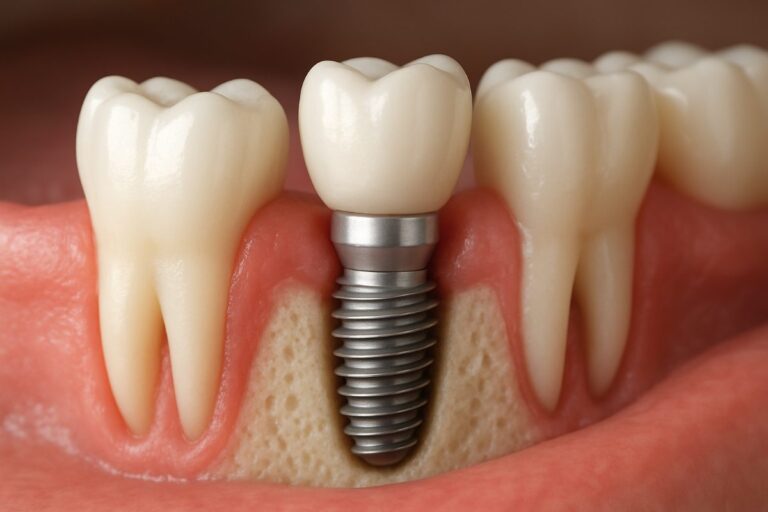

Dental implants are a lasting way to replace missing teeth. They act like tooth roots, hold crowns or bridges, and feel more natural than dentures.

Teeth implants are artificial tooth roots placed in the jaw to hold a replacement tooth or bridge. This 2024 guide explains what teethimplants are, who

Curious about what is a tooth implant procedure? At its core, a tooth implant involves placing a titanium post into the jawbone, acting as a

Dental implants have revolutionized the way individuals approach tooth restoration, offering a reliable and effective solution for missing teeth. These implants are small titanium posts